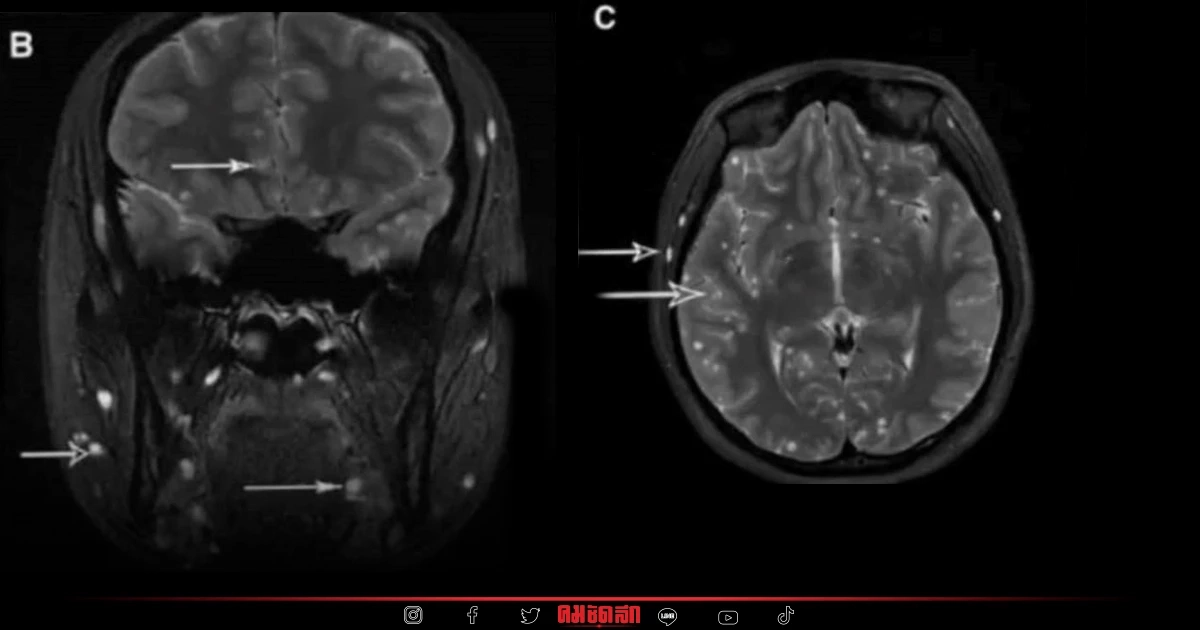

เฟซบุ๊ก หมอแล็บแพนด้า ได้แชร์เรื่องราวสุดแปลกเมื่อสาวรายหนึ่งอยาก "ลดน้ำหนัก" จึงใช้วิธีสุดแปลก เพื่อให้น้ำหนักตัวลดลงอย่างรวดเร็ว แต่วิธี "ลดน้ำหนัก" ของเธอนั้นช่างแปลก และเป็นอันตรายต่อร่างกายเอามาก ๆ โดย หมอแล็บ ได้โพสต์ภาพฟิล์มเอกซเรย์ของผู้ป่วยหญิงสาวคนหนึ่ง หลังกิน พยาธิตืดวัว เข้าไปเพราะหวังจะช่วย "ลดน้ำหนัก" ปรากฎว่าอันตรายอย่างมาก โดยในภาพที่หมอแล็บโพสต์ มีข้อความระบุว่า

หมอแล๊บแพนด้า ยังระบุเพิ่มเติมเรื่องราวของผู้ที่อยาก "ลดน้ำหนัก" ว่า ผู้ป่วยคนนึงอยากผอม ก็เลยไปเอาไข่ พยาธิตืดวัว (Taenia saginata) มากิน ซึ่งอย่าไปเลียนแบบเด็ดขาดนะครับ การกินไข่พยาธิตัวตืด ถือว่าอันตรายมากๆ ถ้าเรากิน ไข่พยาธิตัวตืด ไข่พยาธิมันจะค่อยๆโตเป็นระยะตัวอ่อนเม็ดสาคูแทรกอยู่ในร่างกายคนตามอวัยวะต่างๆ เช่น สมอง ตา หัวใจ ปอด และกล้ามเนื้อ ซึ่งตัวอ่อนเม็ดสาคูในร่างกายเราจะเรียกว่า ซิสติเซอร์โคซิส (cysticercosis) ถ้ามันไปอยู่ในอวัยวะที่สำคัญๆ เช่น ในสมองและไขสันหลัง จะเรียกว่า (neurocysticercosis) หรือถ้าเข้าตาก็อาจตาบอดได้ (ocular cysticercosis) บางรายก็ถึงตายได้เลยนะครับ "อย่าหาทำ"